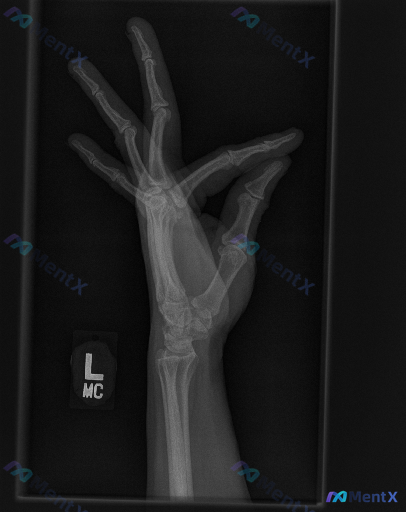

整理到一张左手X光的影像资料,大家可以一起讨论下解读思路: - 影像标记为“L”,是左手的投照 - 但不是标准的正位/侧位/斜位,而是手部处于“OK”手势(拇指与食指捏合)的特殊体位 - 图像清晰度尚可,能看到基本骨性结构 - 当前投照下,各掌骨、指骨骨皮质连续,未见明显骨折线或脱位;关节间隙也没有...